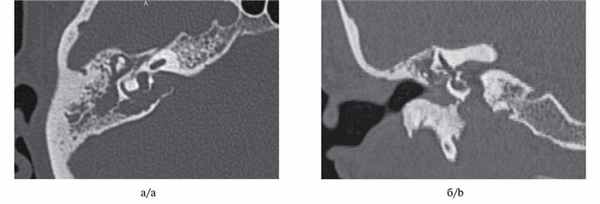

Холестеатома аттика (перфорация ненатянутой части перепонки): КТ в А. Аксиальной и Б. коронарной проекции.

Передняя часть латеральной стенки аттика разрушена мягкотканым массивом, распространяющимся латерально к косточкам,

которые частично разрушены и смещены в медиальном направлении. Холестеатома при перфорации в натянутой части: А. Аксиальная и Б. Коронарная проекции КТ.

Задняя часть латеральной стенки аттика разрушена мягкотканым массивом, заполняющим задневерхний квадрант барабанной полости и заднюю часть аттика.

Холестеатома расширяет aditus и проникает в antrum, который выглядит увеличенным вследствии эрозии периантральных клеток. А. Коронарные и Б. Аксиальные КТ.

Большая холестеатома с фистулами. Большая холестеатома заполняет барабанную полость и сосцевидный отросток,

разрушает лабиринтную стенку с вовлечением капсулы горизонтального и заднего полукружных каналов.